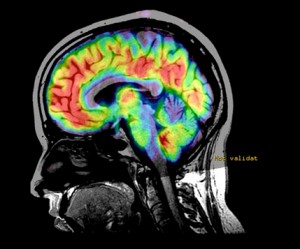

Imagen: El Dr. Ravi Menon, un científico de imágenes del Instituto de Investigación Robarts de la Universidad del Oeste, utiliza RM de susceptibilidad cuantitativa para mostrar y medir el daño producido en áreas específicas del cerebro, lo cual demostró el estudio que es común a todos los pacientes de EM y del síndrome clínicamente aislado (CIS) (Fotografía cortesía de la Universidad del Oeste).

Dirigidos por Ravi Menon, PhD, del Instituto de Investigación Robarts de la Universidad del Oeste (London, Canadá), los investigadores utilizaron una nueva aplicación llamada obtención de imágenes por resonancia magnética (RM) de susceptibilidad cuantitativa (QS), para medir un deterioro de áreas específicas del cerebro, que el estudio mostró que es común a todos los pacientes. Los hallazgos fueron publicados en línea el 28 de mayo de 2014, en la revista Radiology.

En el proceso se utilizó un sistema 3T para RM convencional de Siemens Healthcare (Erlangen, Alemania), así que puede ser reproducido en cualquier hospital, utilizando la técnica, llamada QS. Los investigadores graficaron este parámetro de RM para 25 pacientes con EM recurrente-remitente o con el síndrome clínicamente aislado (CIS. La mitad de las personas diagnosticadas con CIS pasarán a ser diagnosticadas con EM) y midieron la desmielinización y la deposición de hierro. También se examinaron los participantes de control del estudio, de quince años y clasificados por sexo. Mientras que las lesiones cerebrales y de la columna vertebral visualizadas mediante una exploración de RM tradicional tienden a aparecer y desaparecer con el tiempo, la QS reveló áreas de daño que son comunes a todos los pacientes y que se correlacionaban muy bien con la puntuación ampliada del estado de discapacidad (EDSS), la cual es el método estándar que se utiliza para medir la progresión de la EM, así como con la edad y el tiempo desde el diagnóstico.